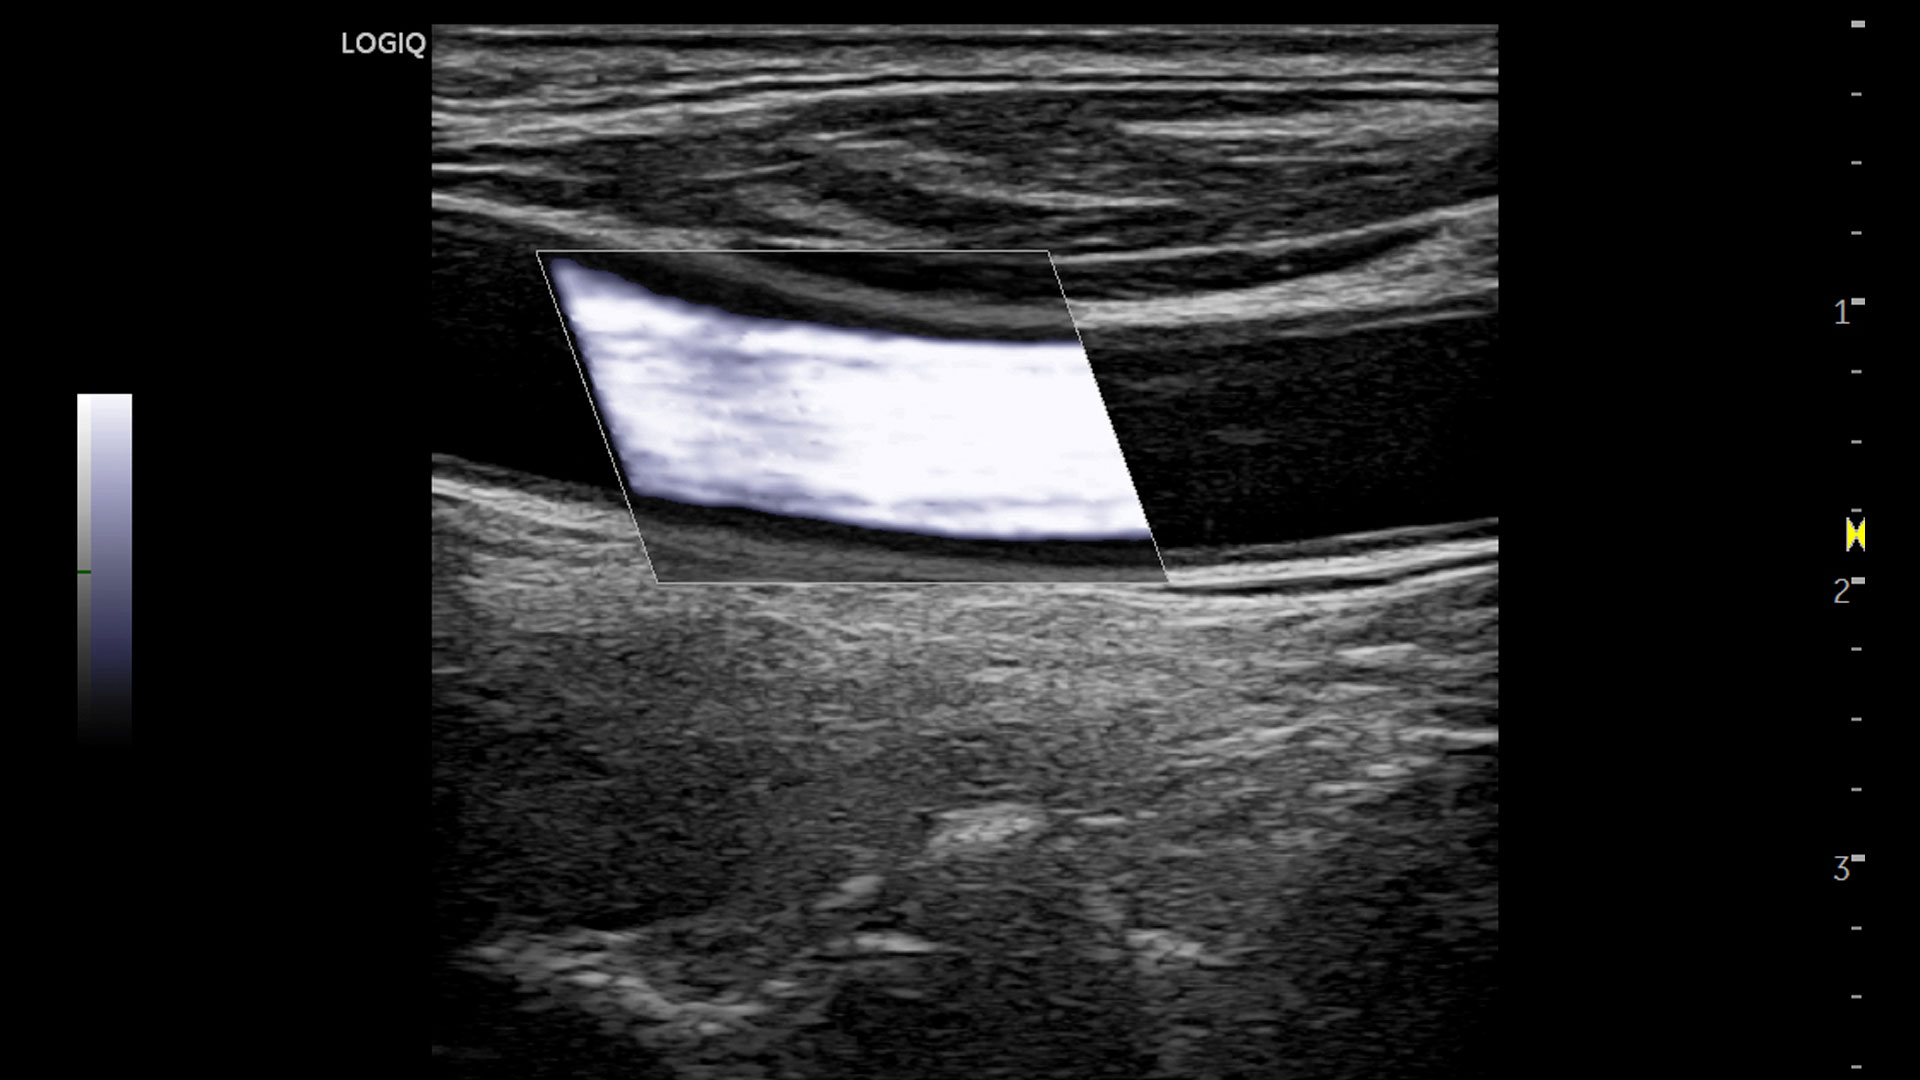

Superb image quality with XDclear probes: Powerful high fidelity and broad bandwidth produce high resolution images whether scanning superficial or deep targets.

• 2D Shear Wave Elastography